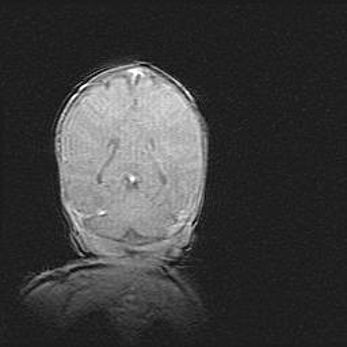

Подострая гематома правой гемисферы мозжечка.

Наружная гидроцефалия.

Возраст: 15 дней

Вес: 3100 г

Пол: женский

Окружность головы: 37 см

Срок гестации: 35-36 недель

При открытой наружной форме гидроцефалии у новорожденных расширяются и переполняются субарахноидные пространства.

Кровоизлияния в мозжечок имеют две клинико-анатомические формы: полушарные гематомы и кровоизлияния в червь.

К появлению этой патологии может привести: повреждения головного мозга, возникающие в результате асфиксии и гипоксии плода при беременности, или травмы во время родов. Редко гематома мозжечка может быть результатом первичной коагулопатии и сосудистой мальформации, диссеминированном внутрисосудистом свертывании, изоиммунной тромбоцитопении.